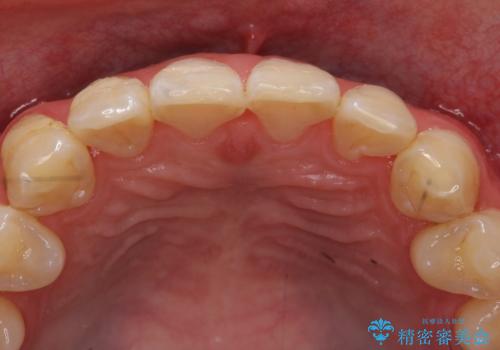

- 右上2、3番目の歯の色・形が気になるといらっしゃった方の症例です。

古い樹脂を除去後、オールセラミッククラウンによる補綴を行いました。